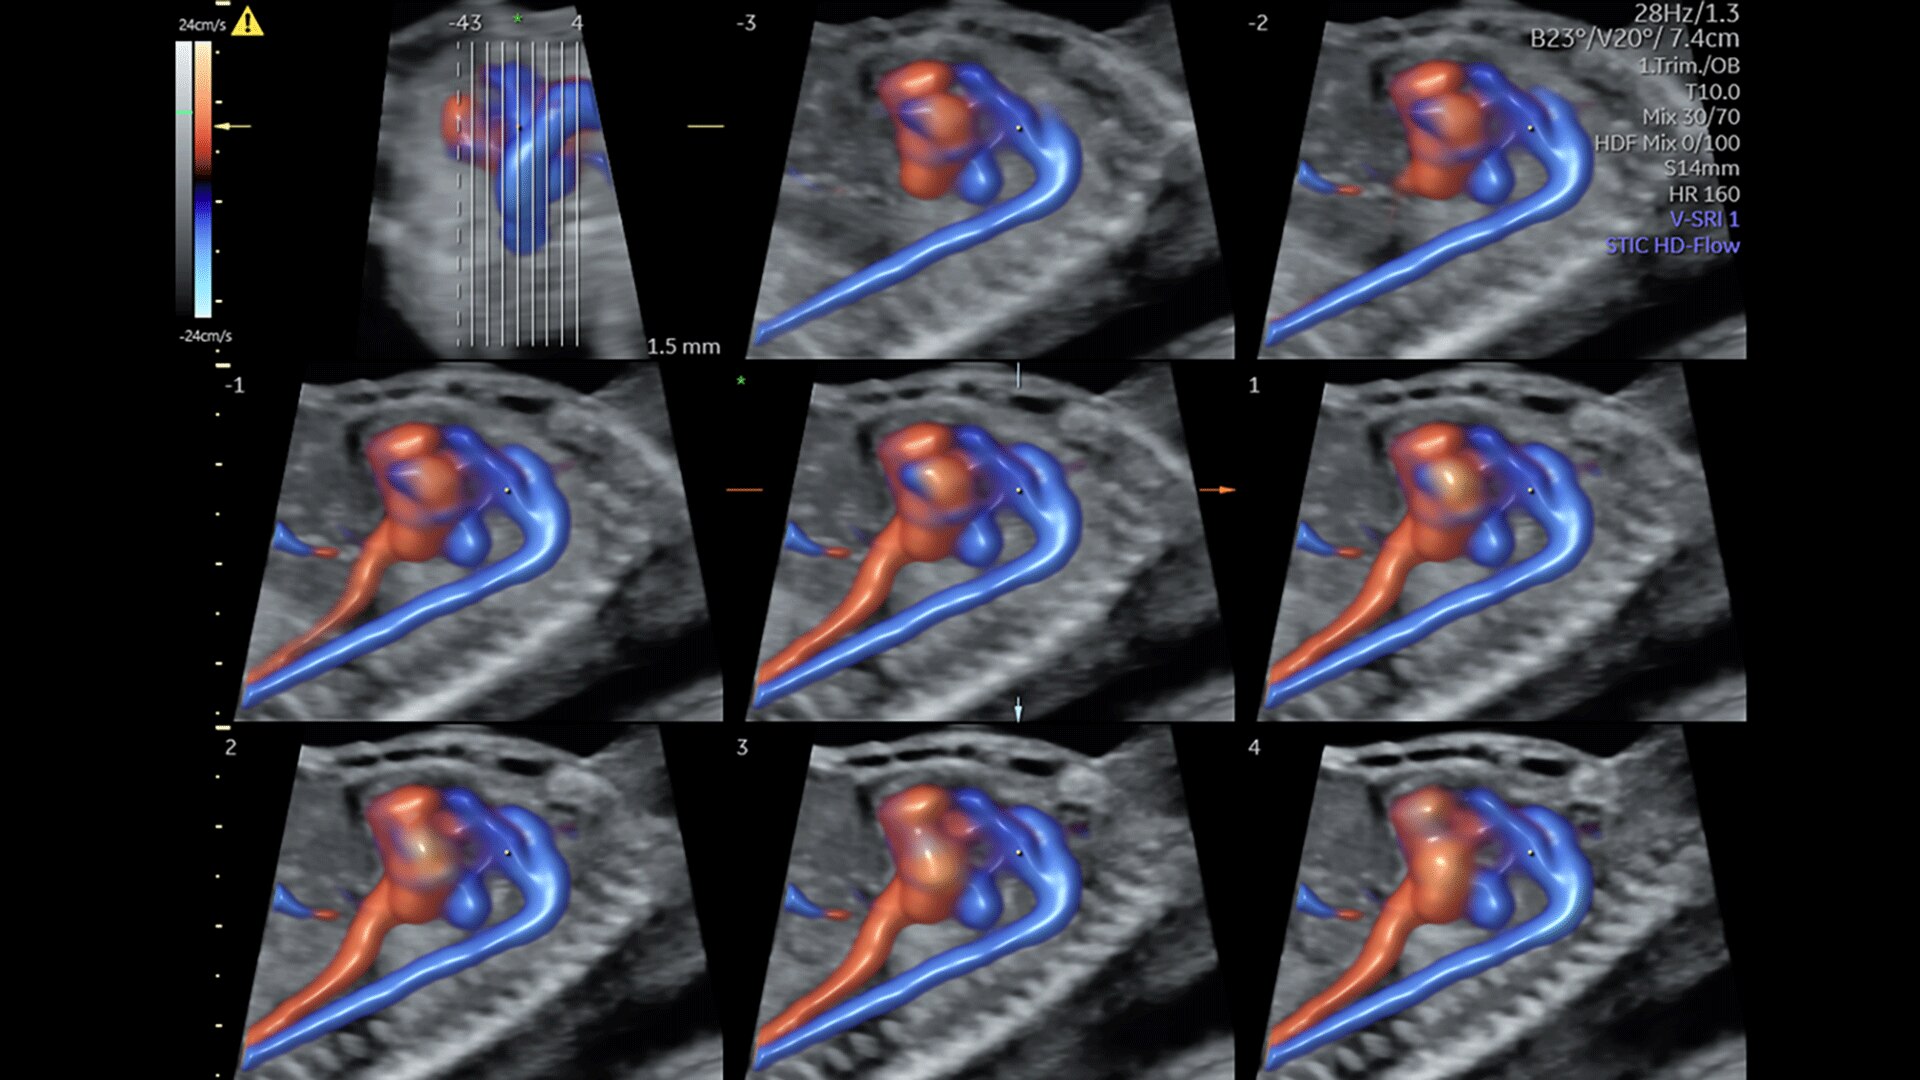

Fetal Heart Assessment

Detect, diagnose, and monitor with confidence using Radiant and fetal HQ

FETAL HEART EVALUATION

Get to the Heart of the Matter

Identifying fetal cardiac abnormalities earlier means you can intervene sooner, plan for delivery, and potentially improve outcomes. The Voluson Expert 22 provides a full solution of progressive tools, to help distinguish the tiniest structures with stunning clarity to provide patient answers faster.